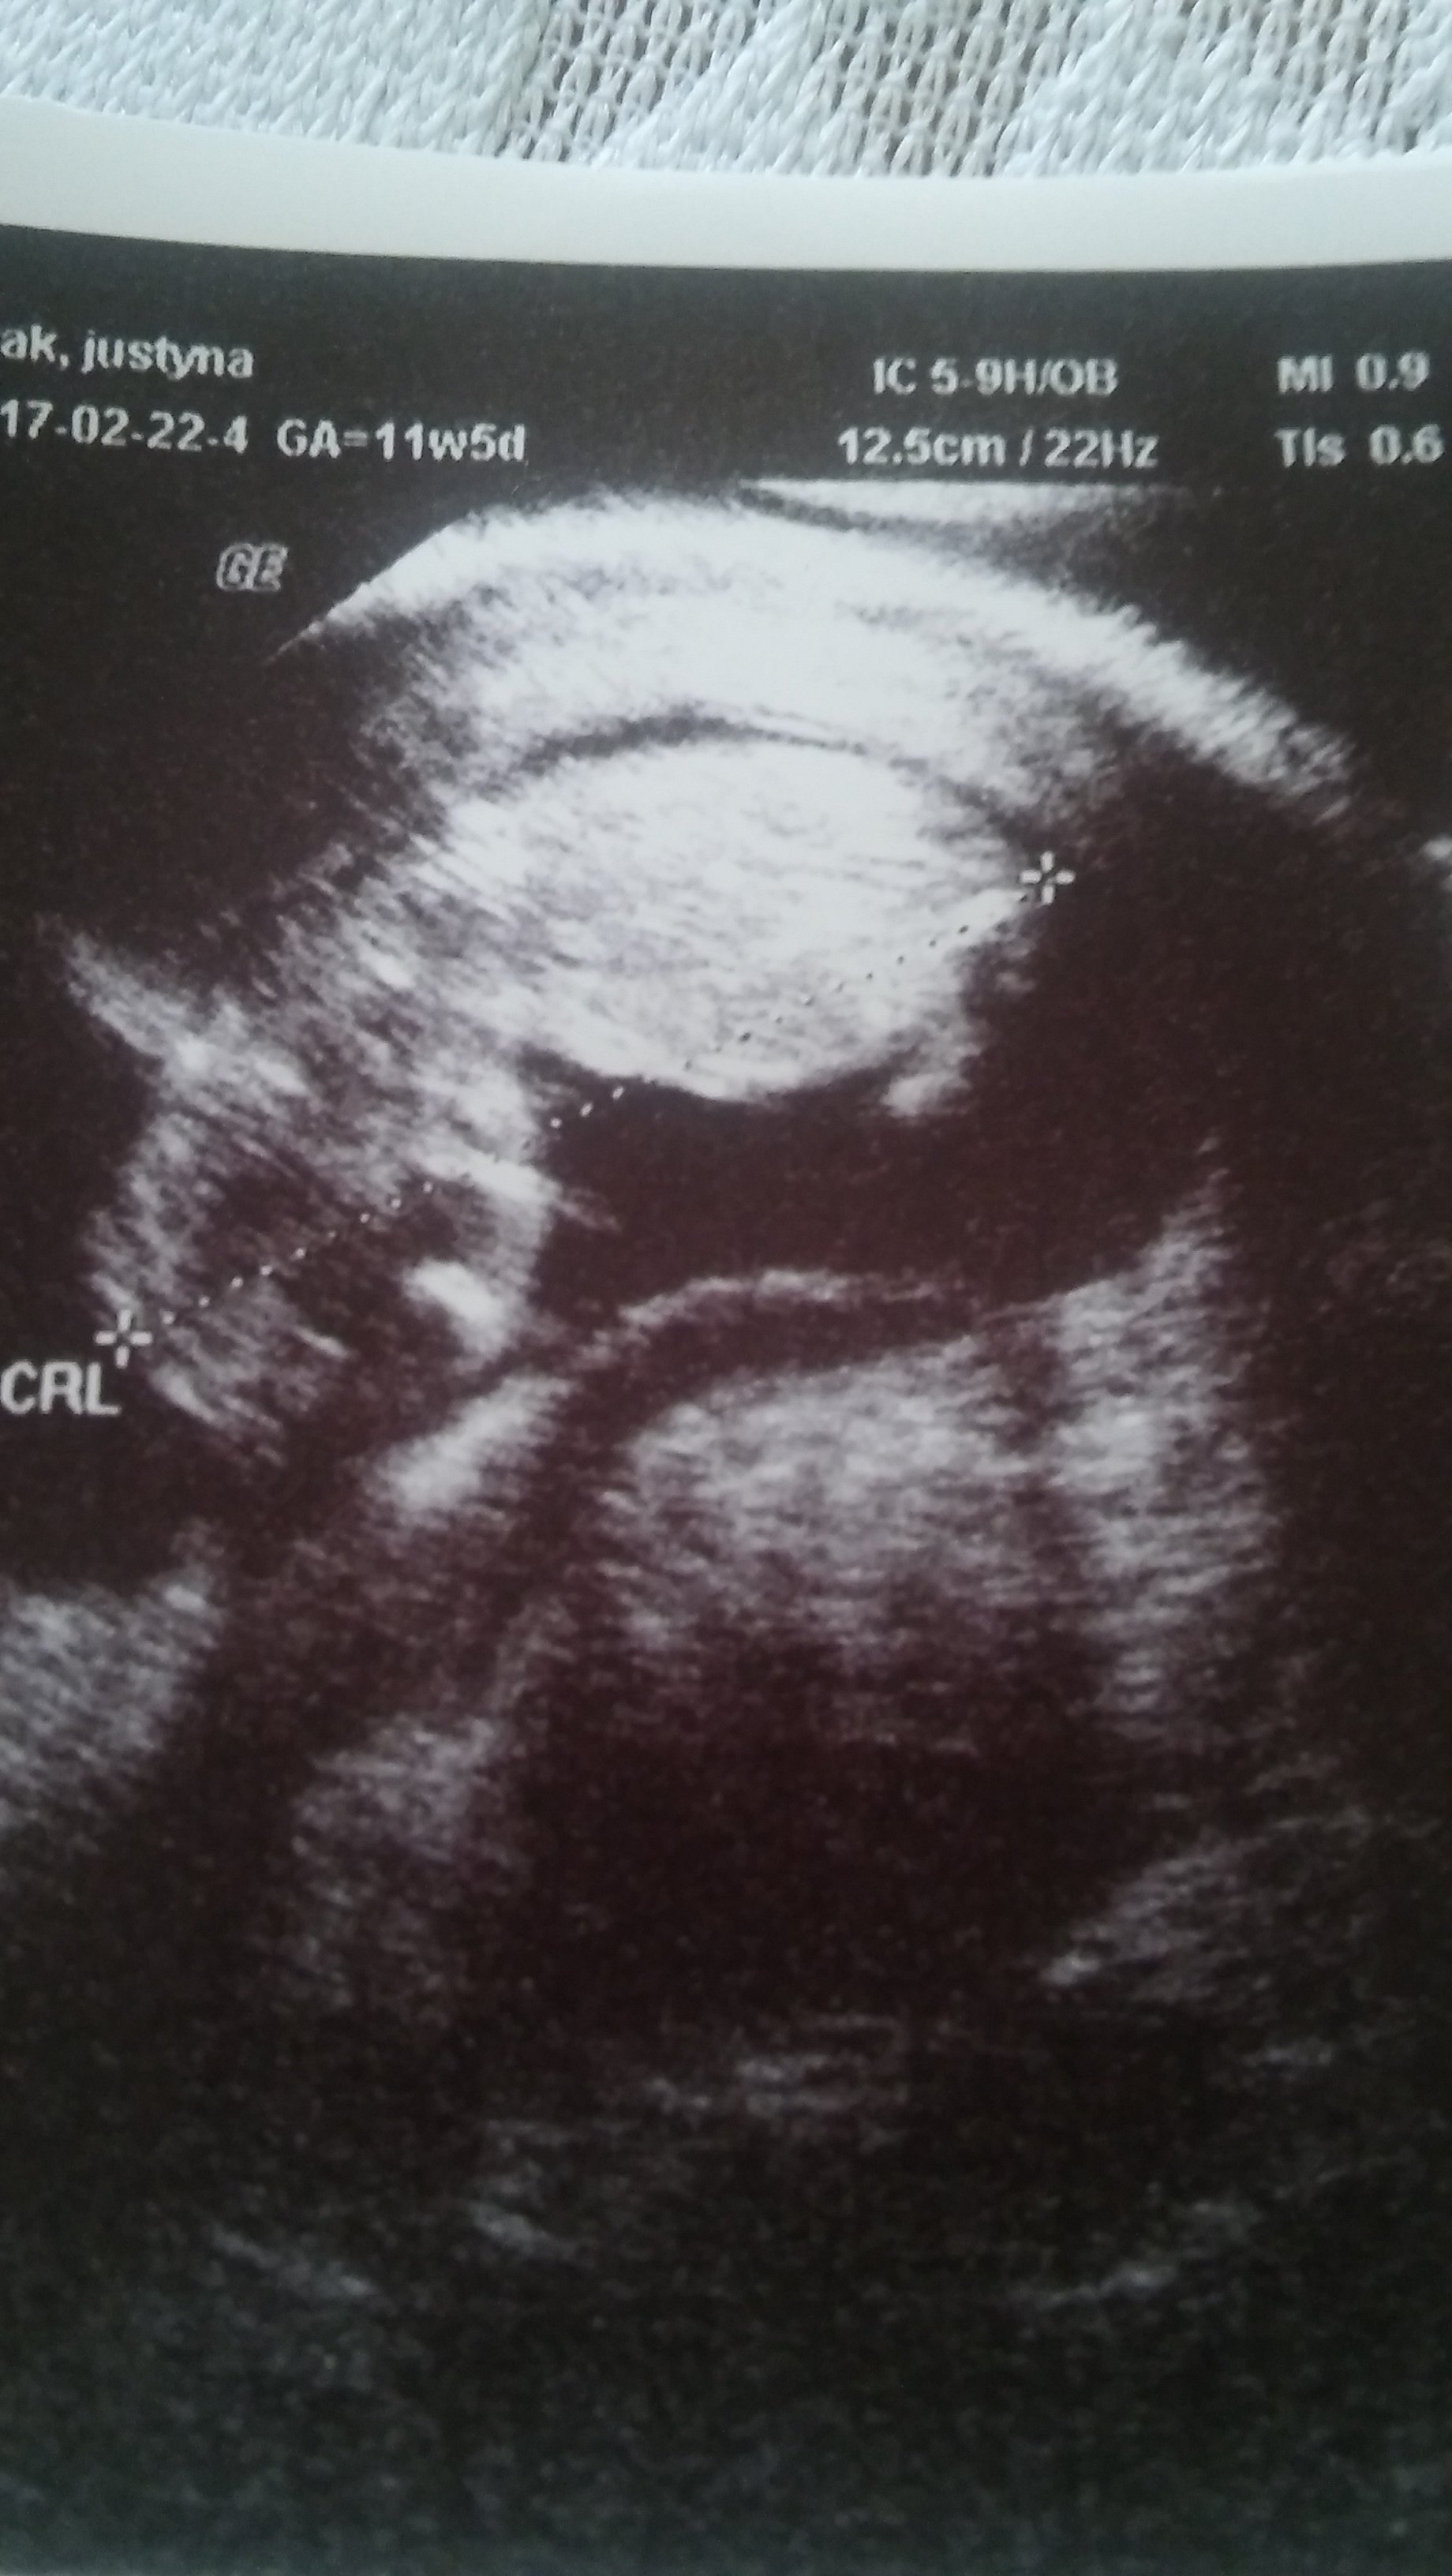

Też się w nocy stresowałam, bo kichnęłam i tak mnie zakłuło w dole w okolicy pi razy gwóźdź jajnika. A potem trochę kłuło w podbrzuszu. Nie mogłam zasnąć, bo sobie zaczęłam nakręcać, że tak kichnęłam, że to mogło zaszkodzić... Wreszcie usnęłam. Dziś nic nie kłuje. Mam nadzieję, że to tylko jakieś durnoty sobie nawkręcałam i to nic takiego. Rany jak ja chcę już na to usg i zobaczyć, że wszystko jest OK!!!!